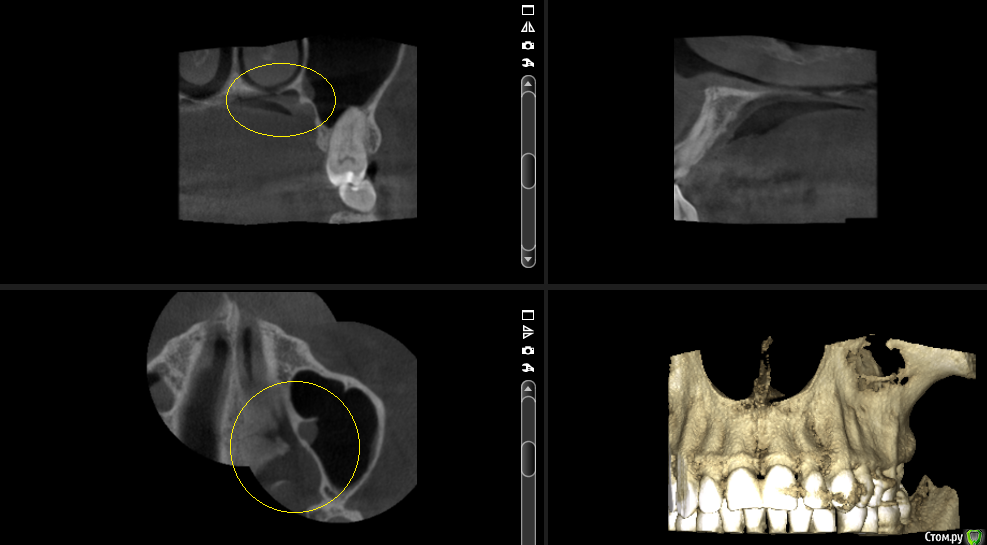

___49___ Опубликовано 19 сентября, 2016 Поделиться Опубликовано 19 сентября, 2016 (изменено) Уважаемые коллеги прошу высказать свое видение предоставленных срезов КТ ...Основной диагноз : Нейропатия второй ветви левого тройничного нерва.Из анамнеза: Пациентка отмечает появление болей (усиливающиеся при движениях левым глазом) в супро, -инфроорбитальной области после лечения 26 го зуба 3 года назад. Неэффиктивность НПВС. Мне не нравится область твердого неба по ходу одноименного нерва : увеличенный свод с диффицитом костной ткани с участками полного ее отсутствия , незначительное утолщение слизистой в верхнечелюстной пазухи и полости носа напротив выше обозначенного участка . . мысли идут в сторону деструктивных изменений связанных с пат.изменениями нервной ткани второй ветви тройничного нерва . . поделитесь своими мыслями .... Изменено 19 сентября, 2016 пользователем ___49___ 2 Ссылка на комментарий